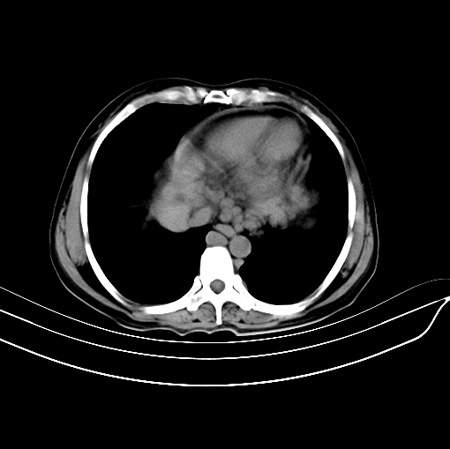

以下是引用江尾海头在2007-9-7 19:01:00的发言:[br]肝叶比例失调,肝边缘高低不平,尾状叶增大,肝裂增宽。肝右叶见较大密度减低影,边缘欠清。脾脏明显增大,胃底及奇静脉半奇静脉曲张。胆囊未见明显显示。 考虑:1、肝癌。2、肝硬化伴脾大静脉曲张。

以下是引用zhangxu5888在2007-9-7 22:31:00的发言:[br]1、肝硬化,食管 胃底及奇静脉半奇静脉曲张;2、脾脏肿大; 3、肝右叶的病灶呈锲性改变,内可见条片状钙化,边界清晰,密度明显低于周围正常肝组织,我觉得肝癌可能性不是很大, 同意楼上观点,有可能是栓塞,建议增强.